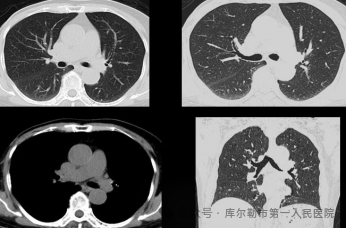

3、微剂量体检筛查-解除您的后顾之忧

采用源头低千伏成像模式,超高端320排CT可实现肺部、冠脉等全身各部位大扫描通量、微辐射剂量的体检筛查。低千伏扫描模式可以有效降低辐射剂量和对比剂用量,降低肾功能不全受检者增强检查风险,系统还可根据不同患者体型和扫描协议自动推荐扫描管电压,在降低患者扫描剂量的同时,优化对比度噪声比。